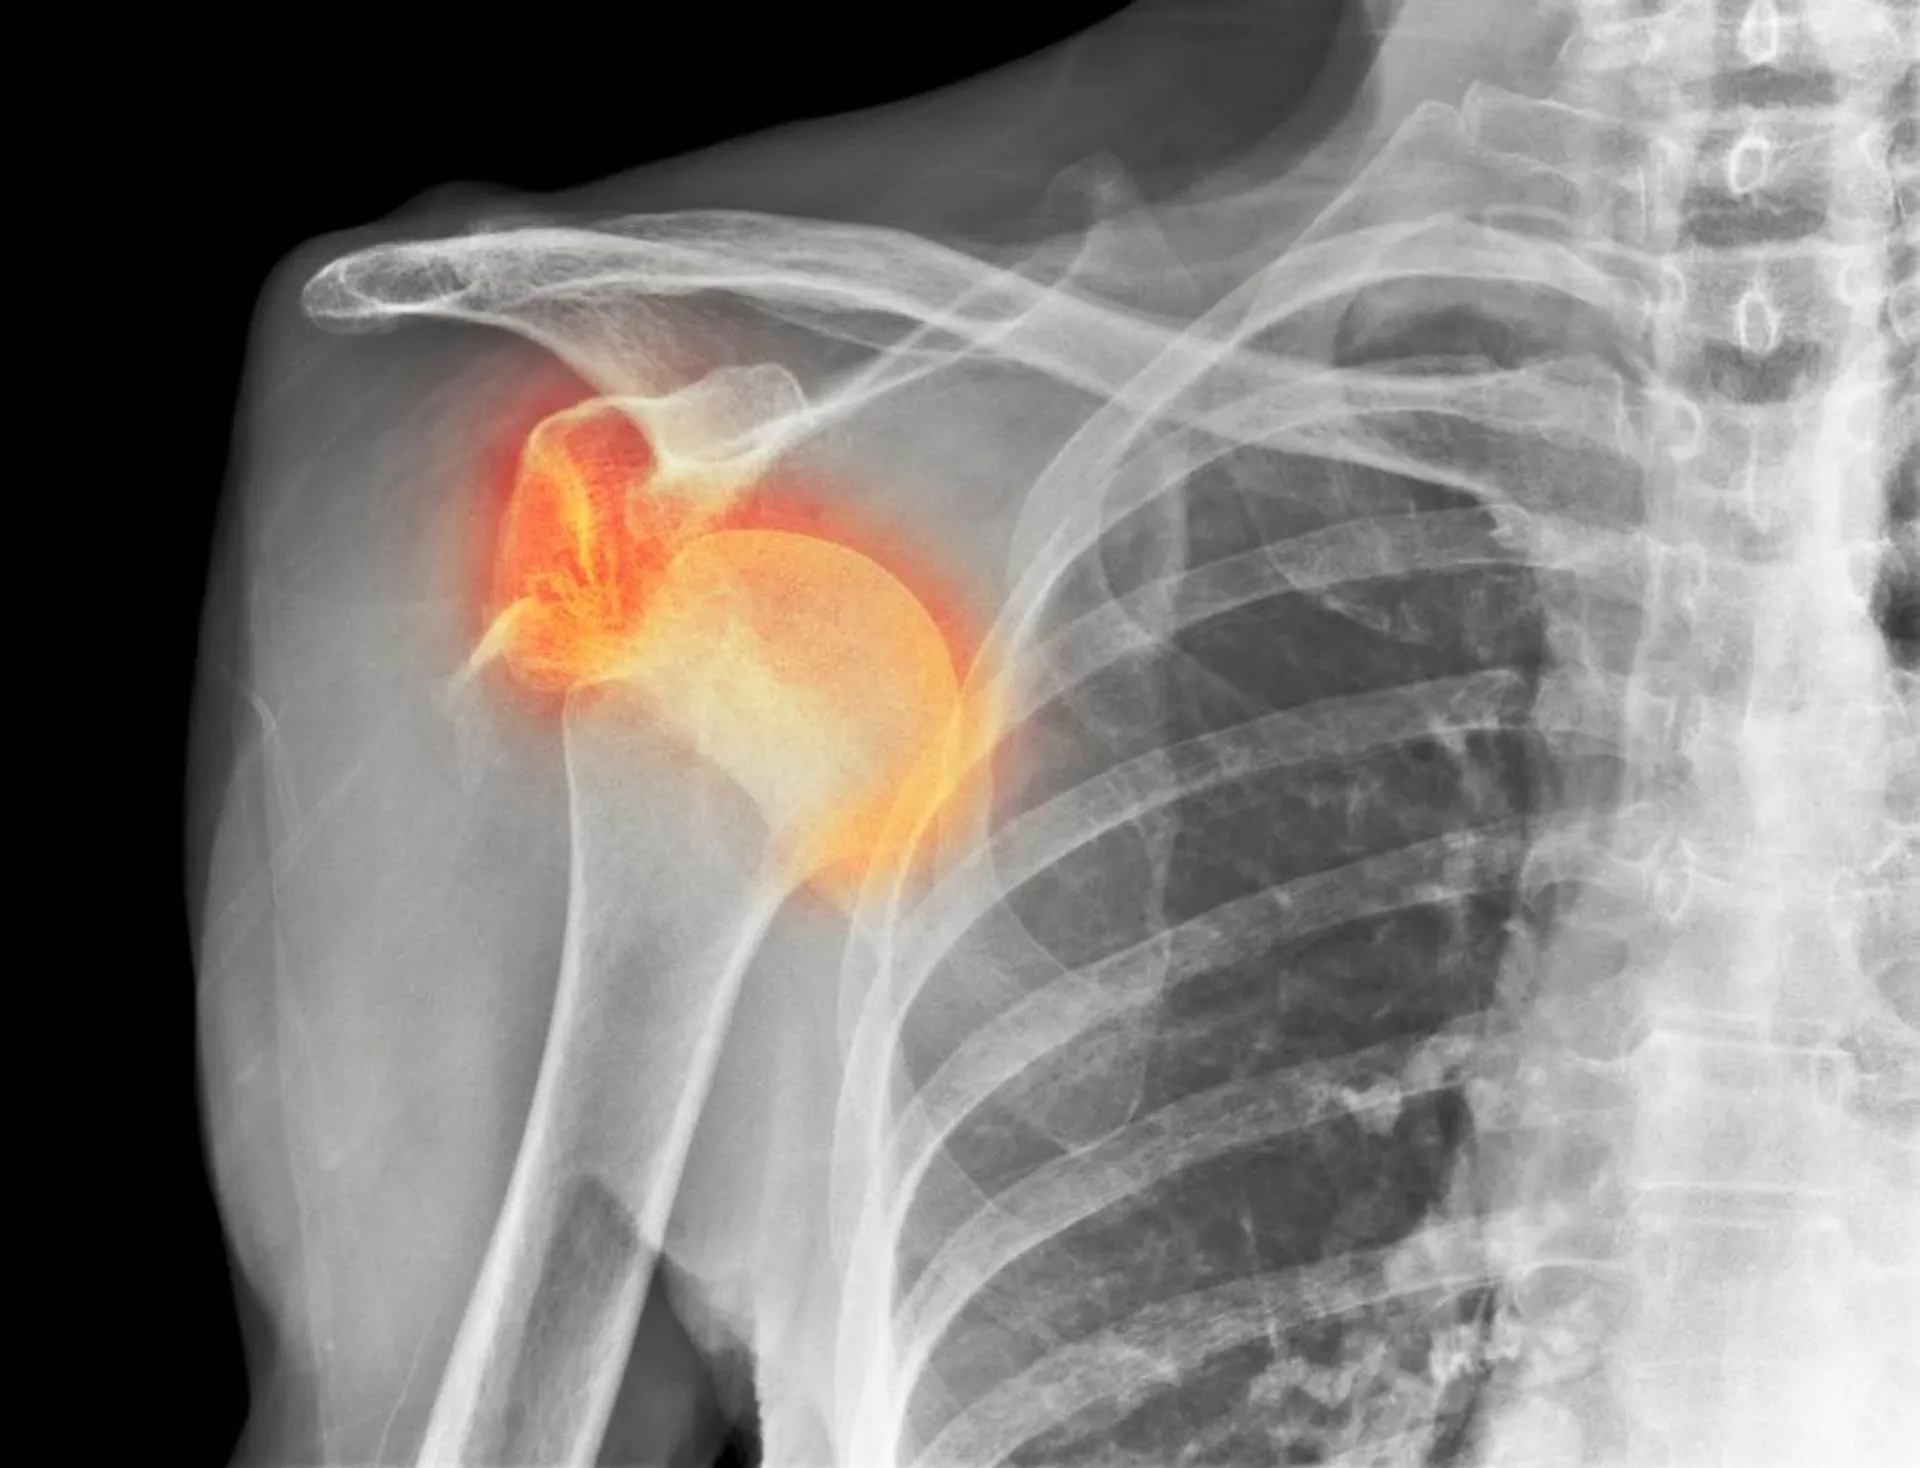

La luxation d'épaule survient lorsque la tète de l'humérus sort de sa cavité articulaire sur la scapula.

Cela peut se produire à la suite d'un traumatisme direct, comme une chute ou un impact lors d'un contact.